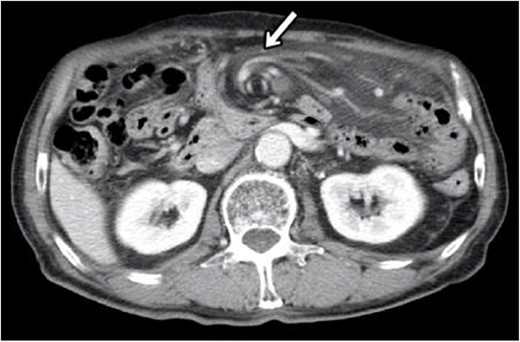

Blood tests showed no elevated inflammatory findings (white blood cell count, 5.7 × 109/l, and C-reactive protein level, 0.15 mmol/l). Computed tomography (CT) of the abdomen and pelvis was performed (Fig. 1), revealing a small amount of ascites in the Douglas fossa, a whirl sign of the superior mesenteric artery (SMA), and branches wrapped with the adjacent mesentery and small bowel loops, all characteristic of SBV. Therefore, a diagnosis of SBV was made, emergency surgery was performed.

CT at initial diagnosis. CT revealed a whirl sign of the SMA and branches wrapped with the adjacent mesentery and small bowel loops, which are characteristic of SBV (allow).